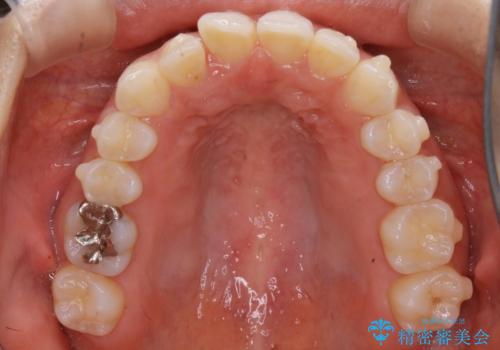

【非抜歯】下の前歯が1本少ない場合の矯正治療

- 前歯のガタつきを主訴に来院されました。

生まれつき下の前歯が1本少なく、その分のスペースを上の前歯がガタつくことで埋めているという状況でした。

上下それぞれのガタつきをとっていく過程で、歯1本分のスペースの差を、上顎の前歯のIPRで調整して並べる方法をご提案させていただきました。